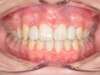

Chevauchement sévère. Traitement multibague sans extraction.

Après